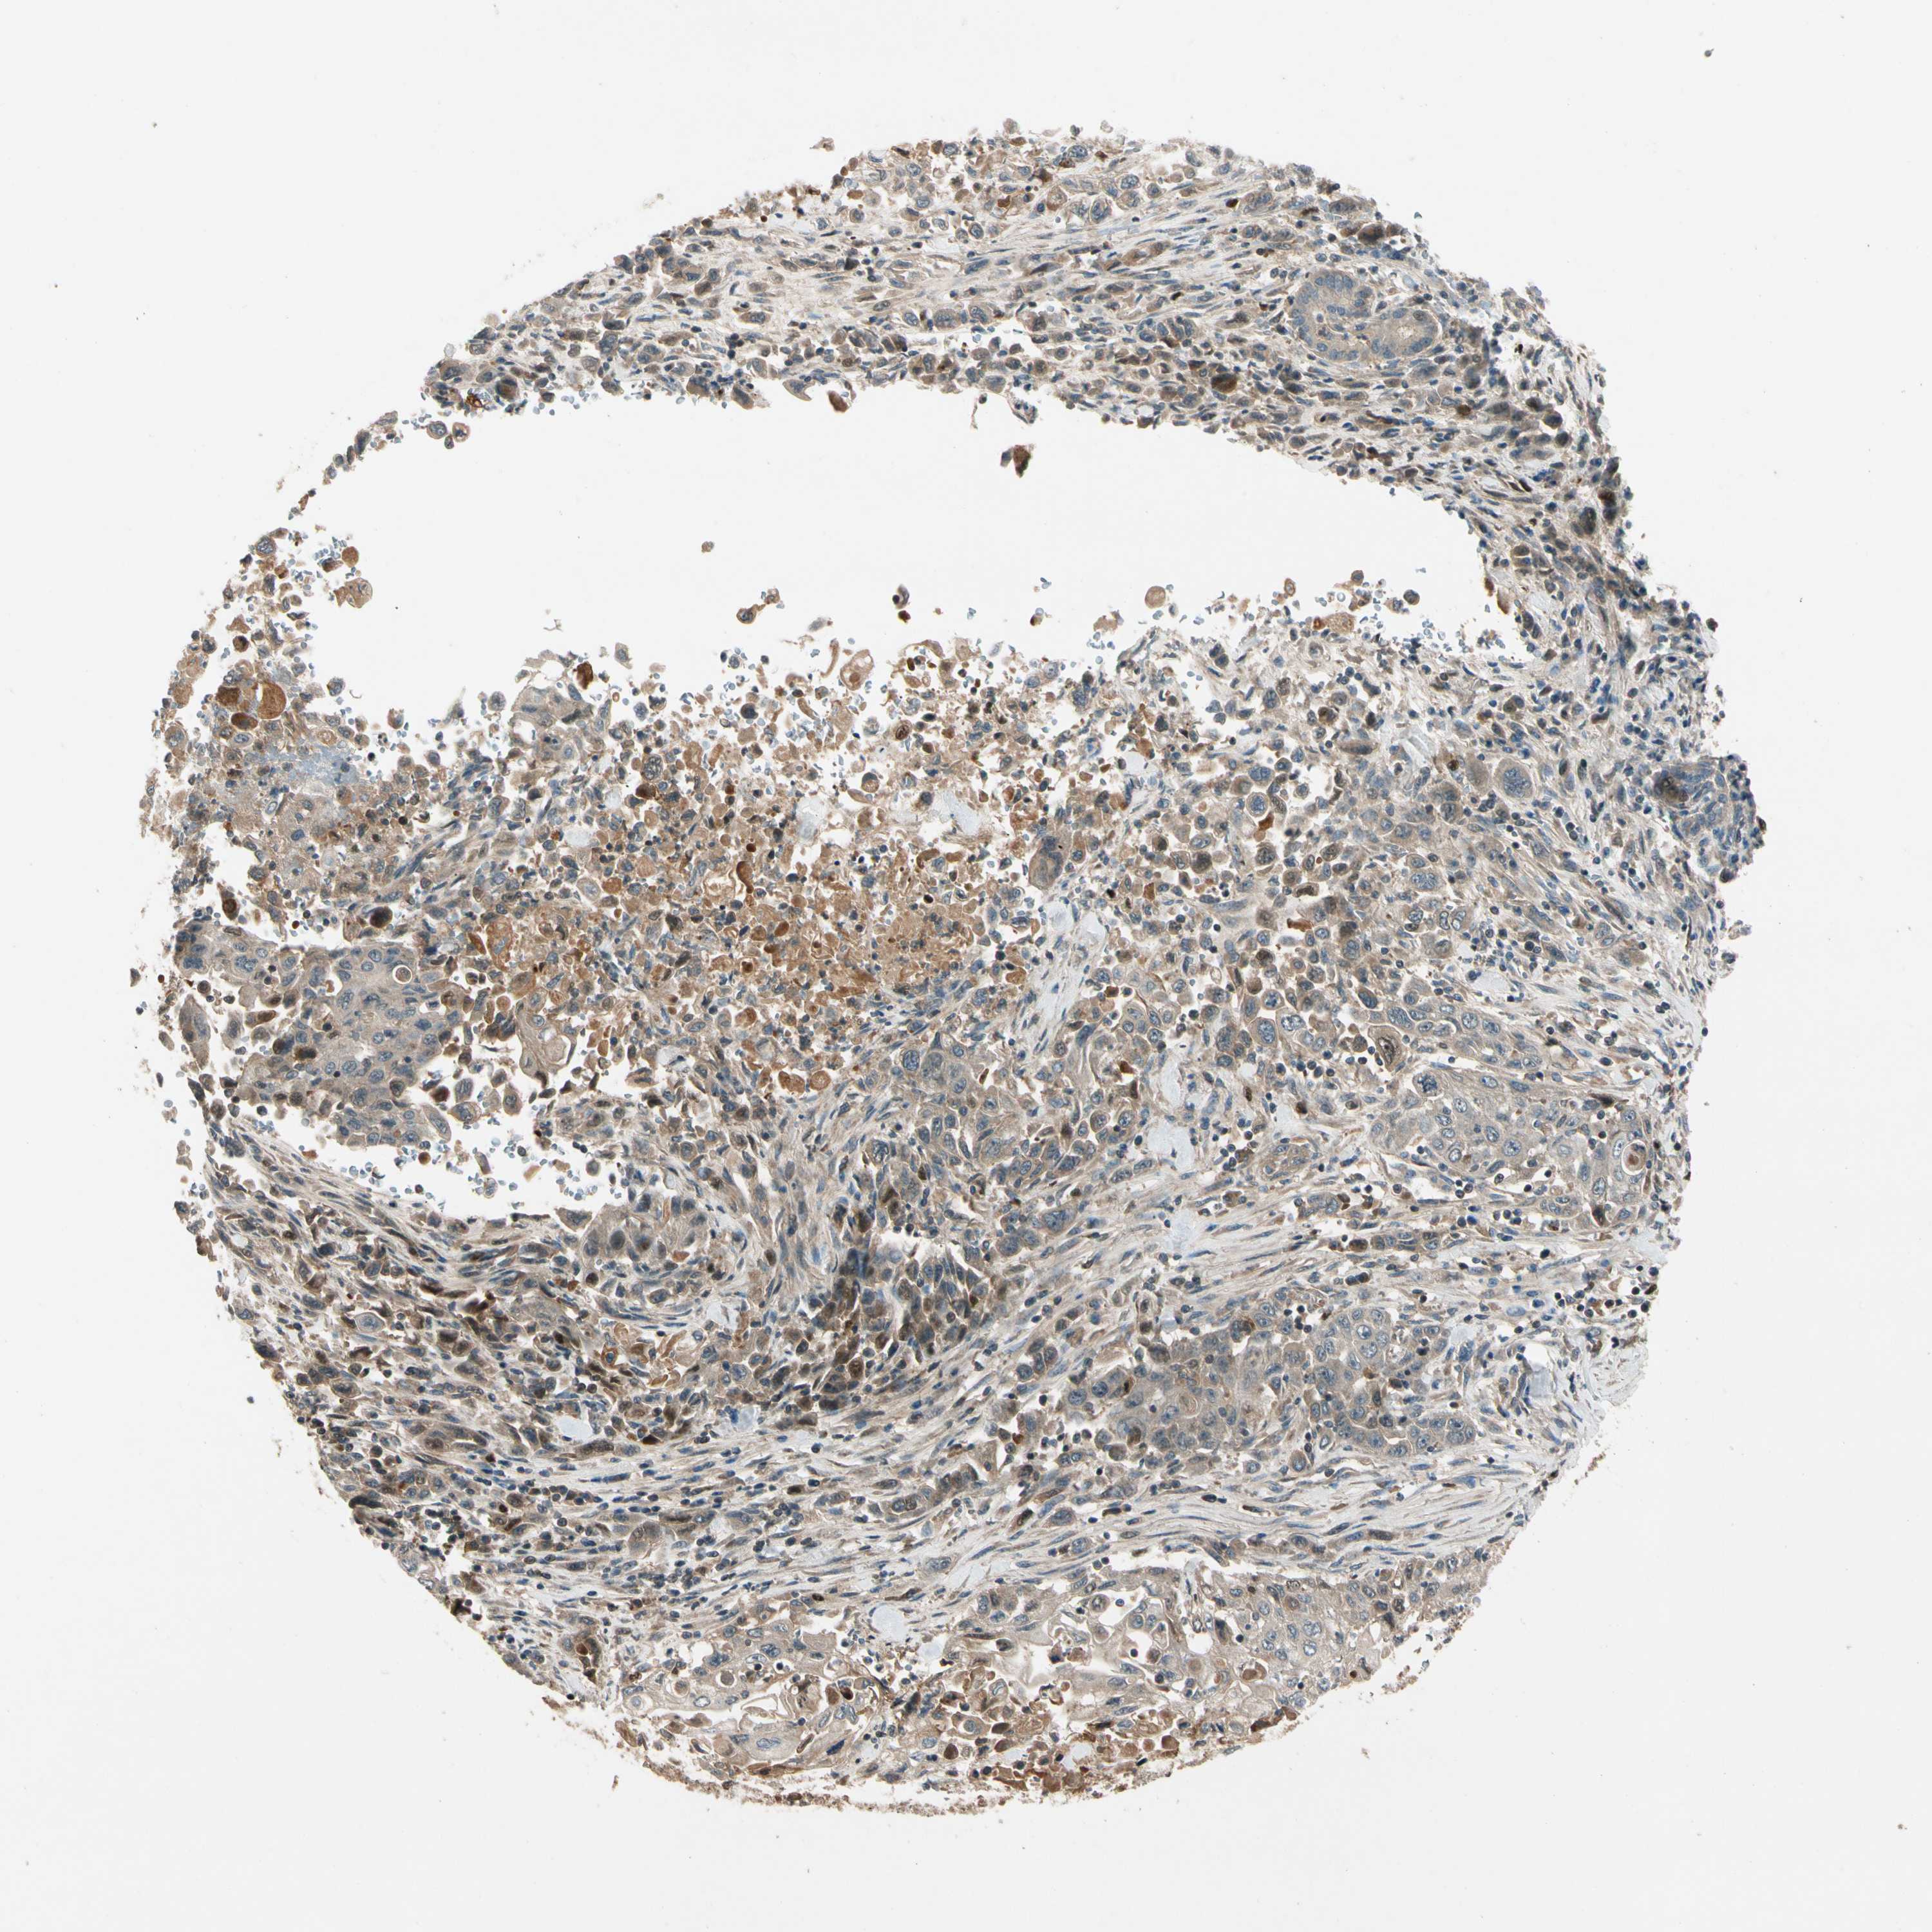

PANCREATIC CANCER - Protein expressioni

A mouse-over function shows sample information and annotation data. Click on an image to view it in a full screen mode. Samples can be filtered based on level of antibody staining by selecting one or several of the following categories: high, medium, low and not detected. The assay and annotation is described here.

Note that samples used for immunohistochemistry by the Human Protein Atlas do not correspond to samples in the TCGA dataset.

Antibody stainingi

Antibody staining in the annotated cell types in the current human tissue is reported as not detected, low, medium, or high, based on conventional immunohistochemistry profiling in selected tissues. This score is based on the combination of the staining intensity and fraction of stained cells.

Each image is clickable and will lead to virtual microscopy that enables deeper exploration of all samples and also displays staining intensity scores, fraction scores and subcellular localization as well as patient and tissue information for each sample.

Antibody HPA007982

Antibody HPA011933

Staining

High

Medium

Low

Not detected

Intensity

Strong

Moderate

Weak

Negative

Quantity

>75%

75%-25%

<25%

None

Location

Nuclear

Cytoplasmic/membranous

Cytoplasmic/membranous,nuclear

Adenocarcinoma, NOS

Adenocarcinoma, metastatic, NOS